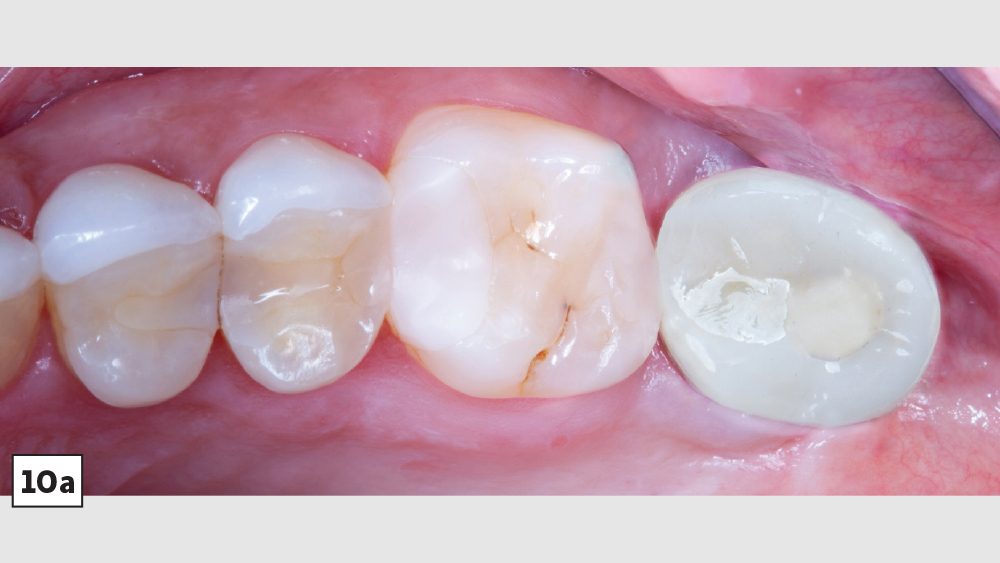

A patient presented with issues concerning a screw-retained crown in the area of tooth #15. She complained that the crown felt loose, was causing food entrapment and was difficult to clean. Upon examination, it appeared that the prosthetic screw was loose and the restoration was mobile. Removal of the crown confirmed that the current design of the prosthesis created a food trap and was not conducive to soft-tissue health. We agreed that the restoration needed to be replaced. A screwmentable restoration was the optimal solution because the malposition of the implant could be corrected by a custom abutment, thereby minimizing the cantilever. We wanted to improve the direction of loading and lessen sheer forces on the implant site by building the restoration out with the titanium structure of the custom abutment. At the same time, because the implant site was in a hard-to-reach area from which cement removal would have been difficult, screw retention was preferred.